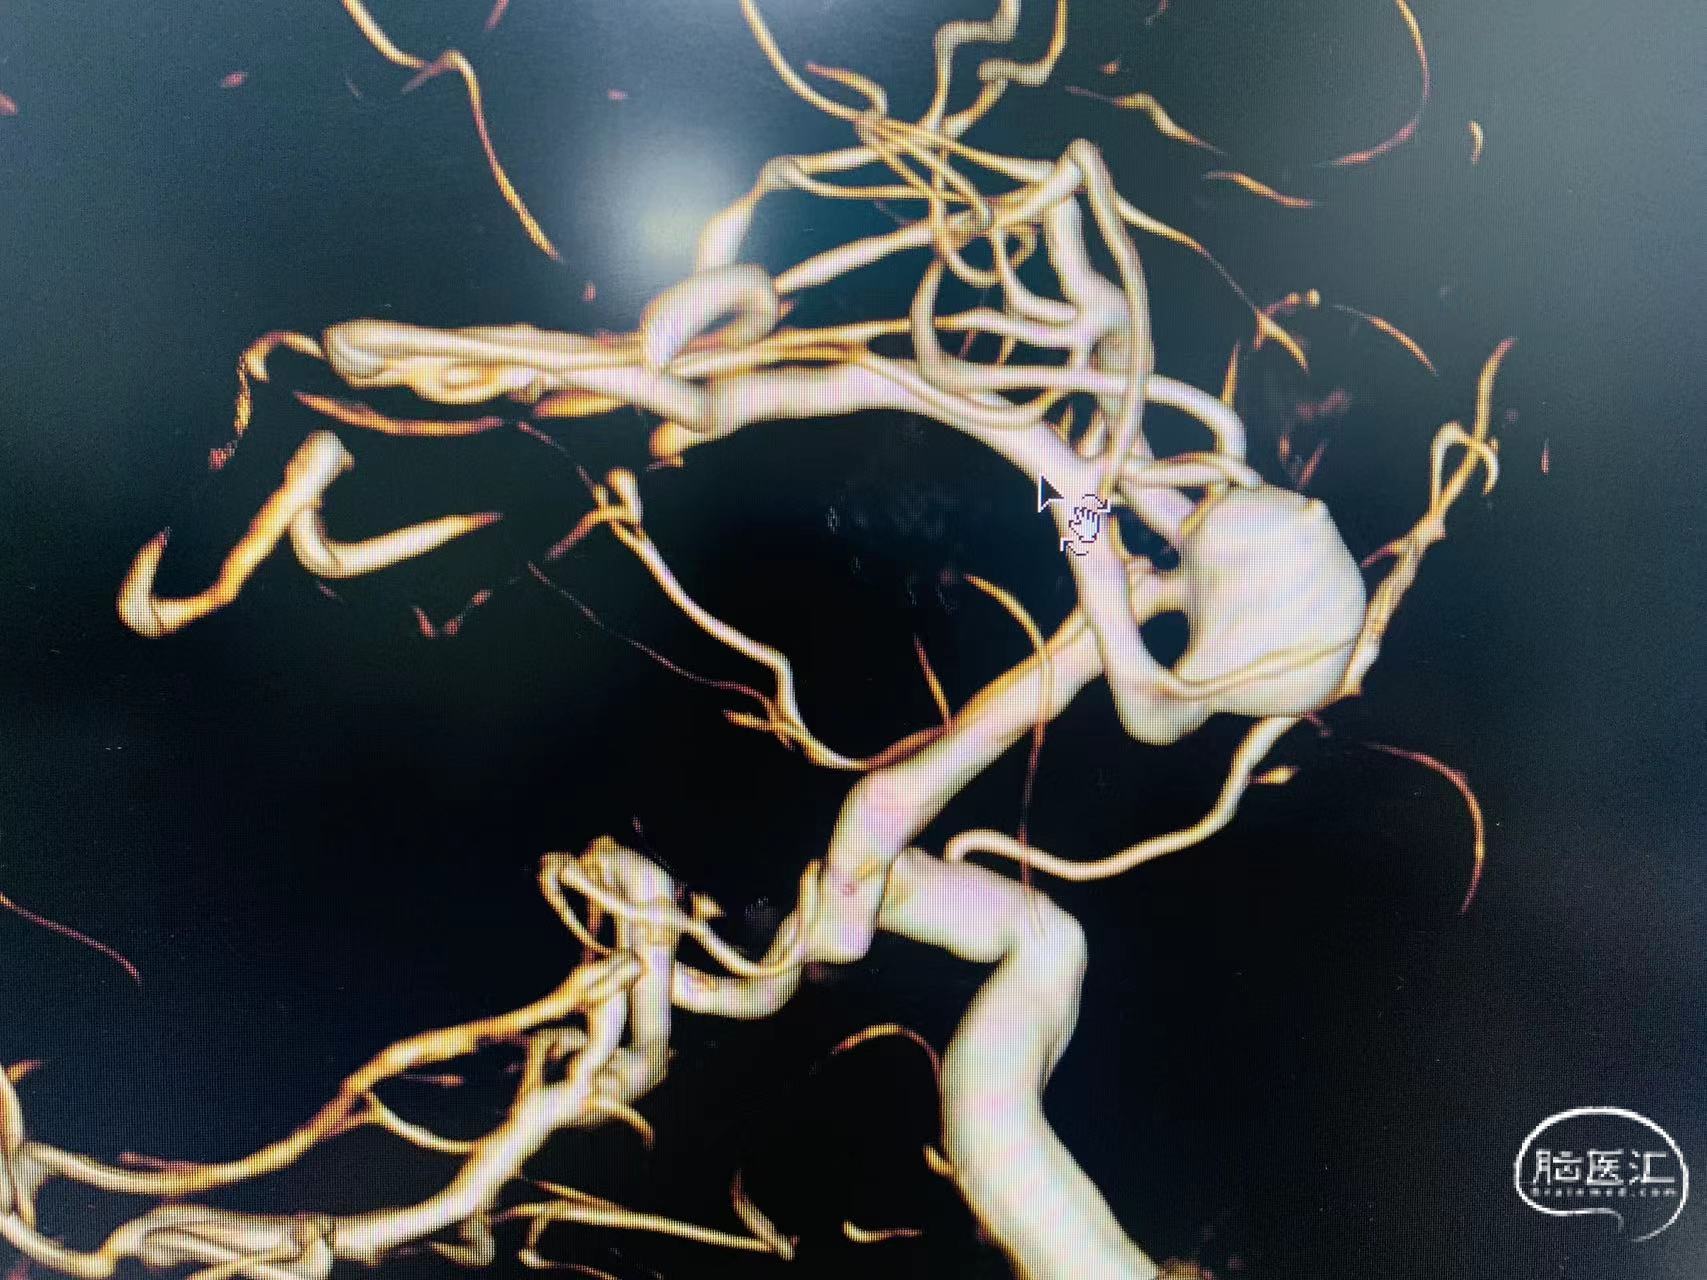

2024-05/11急诊造影见右侧大脑中动脉分叉处有一约你10mm*12mm囊状动脉瘤,表面凹凸不平,基地宽,累计中动脉上下干起始部。

1、动脉瘤特点:位于大脑中动脉,囊性,宽基地,累计中动脉上下干分支起始部;M1远端痉挛/纤细;

急诊行支架辅助下弹簧圈栓塞术,术程顺利。

支架:4mm*39mmETP2、14*35mm、13*37mm、10*30mm、9*30mm、8*30mm、4*10mm、弹簧圈栓塞